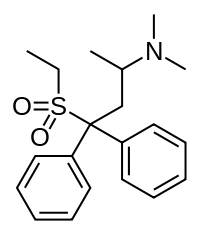

Diphenylpropylamine derivatives

Others